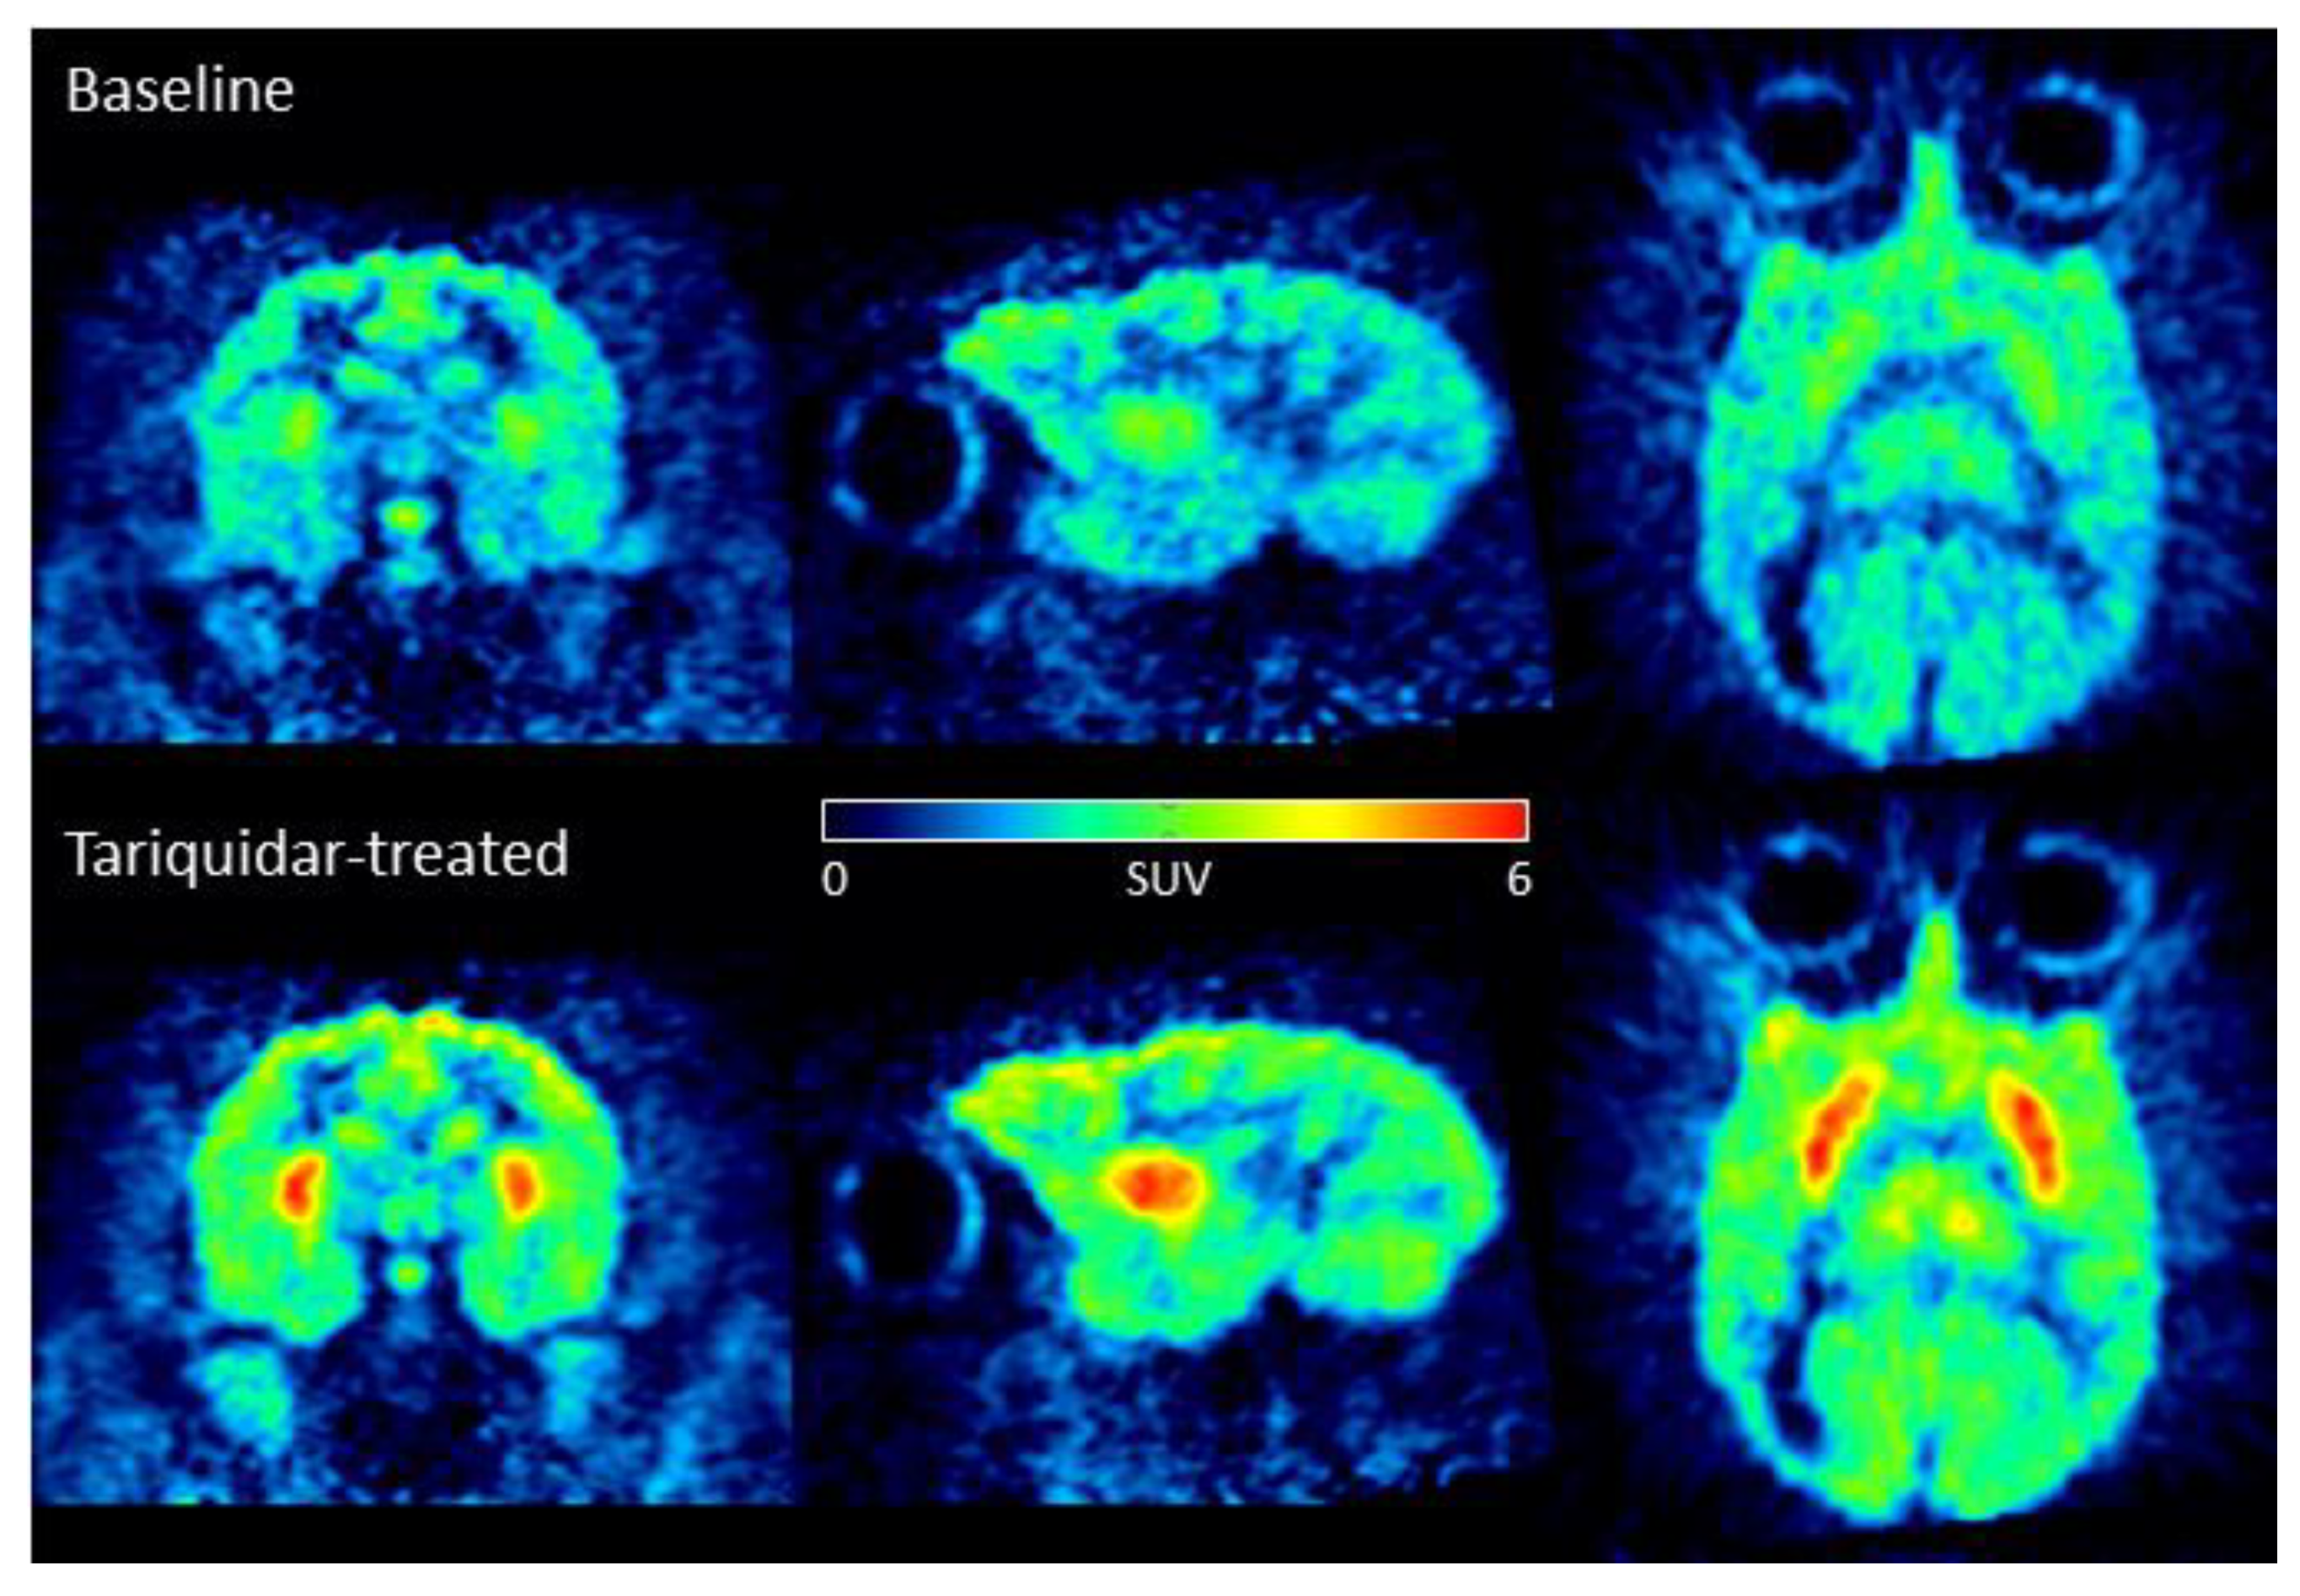

2.4. [11C]1 Is a Brain Efflux Transporter Substrate in Rat, Mouse, and Monkey

| Tissue | [11C]1 Concentration (SUV 1) | |

|---|---|---|

| Baseline (n = 1) | Tariquidar-Treated (n = 1) | |

| Plasma | 0.06 | 0.04 |

| Whole Blood | 0.09 | 0.07 |

| Cerebellum | 1.20 | 2.84 |

| Cortex | 1.33 | 3.49 |

| Striatum | 1.36 | 3.53 |